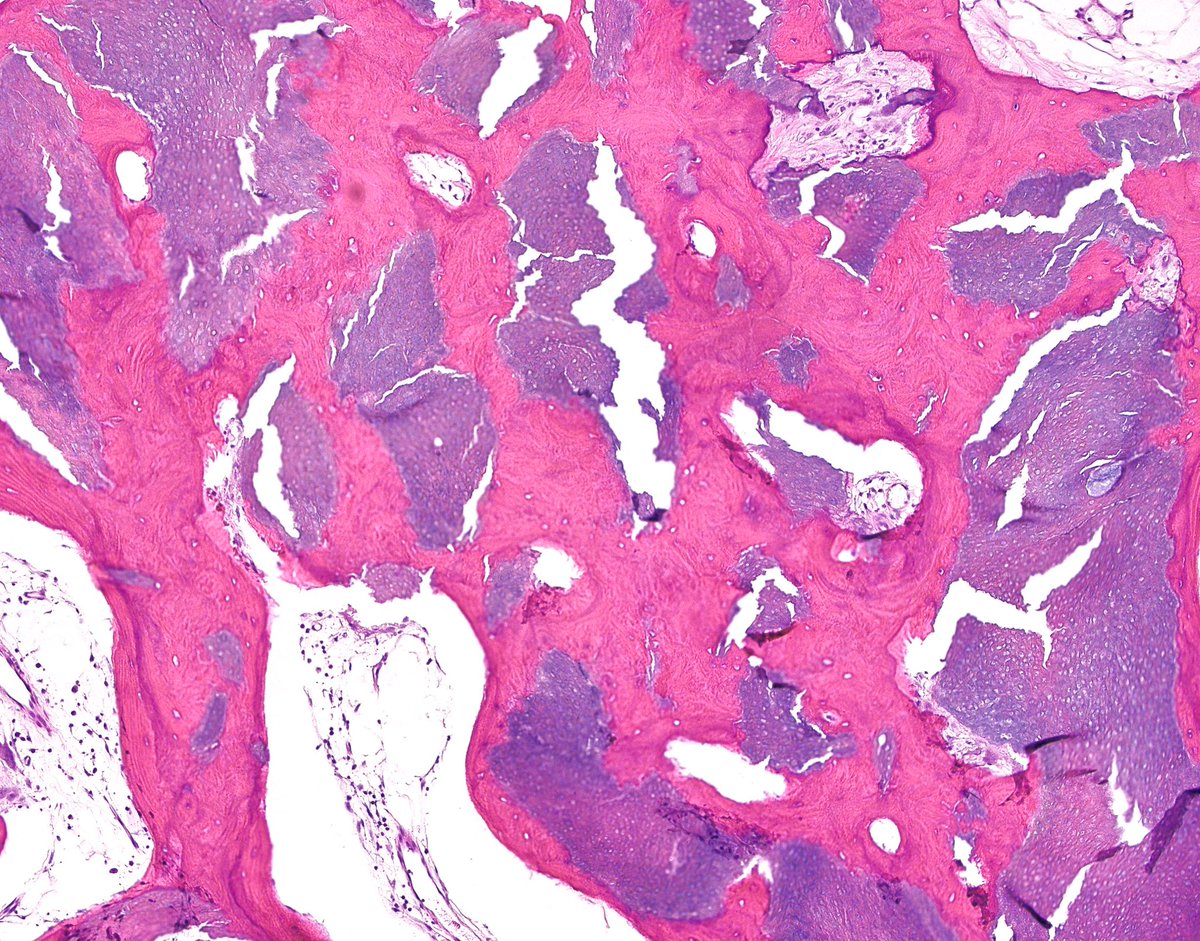

65 yo F 1.5 cm L elbow st mass “r/o gout” CALCIFIED EPITHELIOMA OF MALHERBE WITH OSSIFICATION - firm nodule/mass - keratinized “ghost cells” + bone - focal marrow elements - aka OSSIFIED PILOMATRIXOMA! - aka OSSIFIED PILOMATRICOMA!

#bstpath#dermpath#pathology#nyupathologypic.twitter.com/f3rq7SJIwk